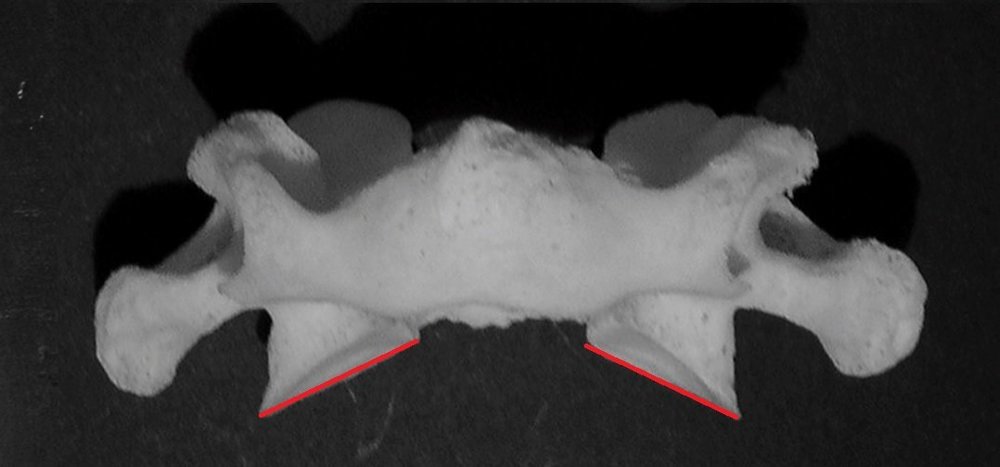

Il n'existe pas, c'est pour ça que c'est faux, on n'a pas de sillon de l'artère vertébrale sur les vertèbres de C7 à C2 car elle remonte dans les foramens transveraires. Au niveau de l'Atlas cette artère va devoir décrire une angulation pour rejoindre la gouttière basilaire de l'os occipital. Et le processus transverse de C1 est unituberculé, donc il n'y a pas de sillon du nerf spinal à cet endroit.

Sinon vu que le sillon de l'artère vertébrale est en-arrière de la fovea craniale, donc il serait en-arrière du sillon du nerf spinal.

J'ai représenté une partie du trajet du nerf spinal.